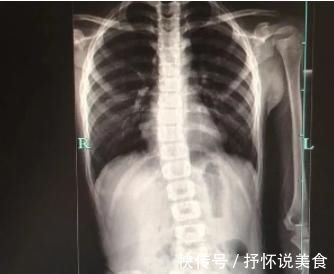

由于早期的脊柱侧弯并没有腰背痛等症状,当家长发现孩子的脊柱已经变得歪歪曲曲时,大部分已是中晚期。所以建议家长每隔一段时间抽出一分钟为孩子做脊柱检查,方法如下:

看孩子的两肩是否等高,若是出现了明显的“一肩高、一肩低”,说明有高低肩的现象。

用手摸一摸孩子背部的肩胛骨,看两块肩胛骨最下端是否等高。

看孩子两侧盆骨是否等高。

让孩子弯腰,家长用中指和食指沿着脊柱突划下来,看是否能划出正常的直线;触摸并对比孩子的腰、背双侧是否有隆起。